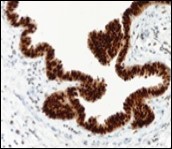

Figure 10.Cutaneous ciliated cyst with nuclear immune reactivity to progesterone receptors (18).

Figure 11.Cutaneous ciliated cyst with immune reactivity to cyto-keratin (19).

Figure 12.Cutaneous ciliated cyst with nuclear immune reactivity to oestrogen receptors (19).

Epithelium of cutaneous ciliated cyst is immune reactive for pan cytokeratin (CKae1/ae3) antigens, epithelial membrane antigen (EMA), oestrogen receptors (ER), progesterone receptors (PR), Wilm’s tumour protein (WT-1) and paired box gene 8 (PAX8). Immune non reactivity is cogitated for S100, smooth muscle actin (SMA), carcino-embryonic antigen (CEA), desmin, thyroid transcription factor(TTF1), p63 and glial fibrillary acidic protein (GFAP).

Smooth muscle actin (SMA) is immune non reactive, thereby suggesting an absence of smooth muscle within the cyst wall. Intense immune reactivity can be cogitated within epithelial nuclei for oestrogen receptors (ER) and progesterone receptors (PR). Aforesaid immune reactions are indicative of Mullerian origin of cutaneous ciliated cyst.